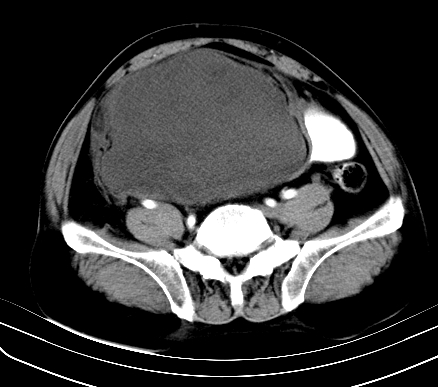

标题: CT19729B:男,74岁,因腿疼就诊,查体触腹部肿物,

增强扫描

延时期

【ct表现】

1、肿块巨大,往往位于腹膜后,长大后才引起症状而就诊;那么位于腹膜后的肿瘤80%为恶性肿瘤。

2、实性肿瘤,增强扫描轻度不均强化,实性肿瘤一般不是好东西。

3、肿瘤边缘似见少许脂肪样密度。

4、腹膜后未见肿大淋巴结,但肿瘤于临近的肠管及组织接触紧密。

【诊断】

腹部占位,考虑位于腹膜后的恶性肿瘤,脂肪肉瘤(实体型)可能性大。

病变基本位于下腹部正中,膀胱有联系。完全是囊性。首先考虑脐输尿管囊肿。

应该是腹腔病变,病灶较大,内可见脂肪密度影,边界较清,有钻孔样改变,表皮强化,考虑畸胎瘤(皮样囊肿)可能性大.

术后病理结果:腹膜后脂肪肉瘤。